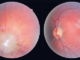

Sindromul opsoclonus-mioclonus

Sindromul opsoclonus-mioclonus - boală neurologică autoimună ce apare ca răspuns la o infecție bacteriană, virală, un vaccin sau o tumoră denumită neuroblastom. Anticorpii ce apar atacă celulele creierului.